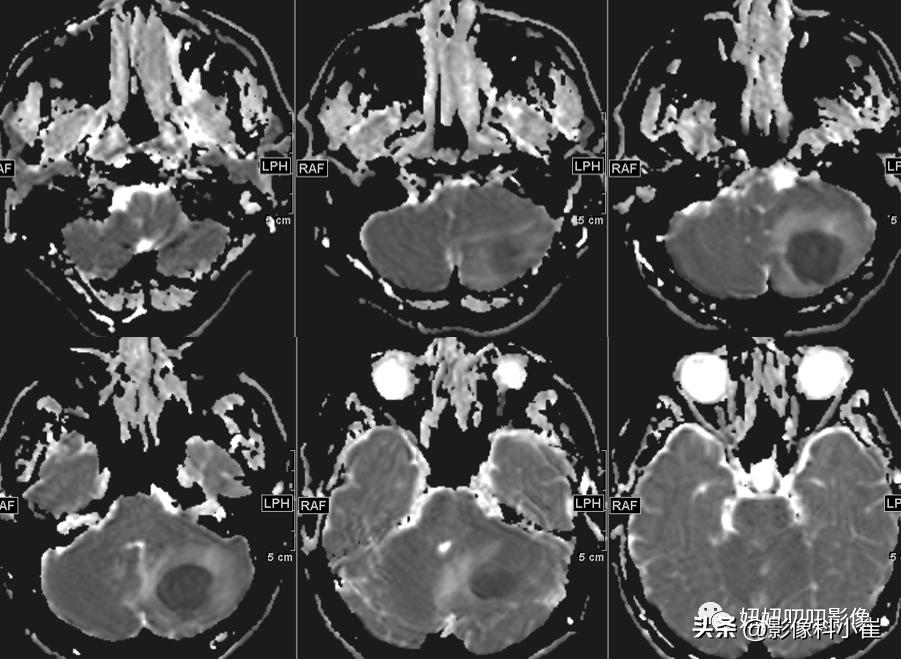

左侧小脑半球片状长短T1等长T2 异常信号,边界不清,大小约3.2X2.9X2.4cm,T2-Flair呈等高信号,周围见斑片状水肿带,DWI 示病变明显弥散受限,增强扫描可见不均匀环状强化。双侧放射冠、皮层下另见少许斑点状等长 T1、长T2 异常信号灶,T2 Flair 呈高信号,DWI未见明显弥散受限,增强扫描未见明显异常强化。第四脑室受压变窄,幕上脑室系统未见明显扩张。脑沟、脑裂略增宽。中线结构无移位。双侧筛窦、上领窦粘膜增厚。

这个病有意思,周边T2黑黑的,弥散受限这么明显,强化还是环形强化,从环形强化入手?转移,胶质母,脓肿。从弥散收入,淋巴瘤,脓肿,胶质母,T1还有出血,信号不均匀,边界清楚。其实看到出血觉得是胶质母,其实看看弥散的均匀度,和环状强化的边,并不是那么花环样子,加上白细胞高,可能还是脓肿。

病理是脓肿;

慢慢对比,看下边界,看下DWI的样子,自己慢慢品!!!